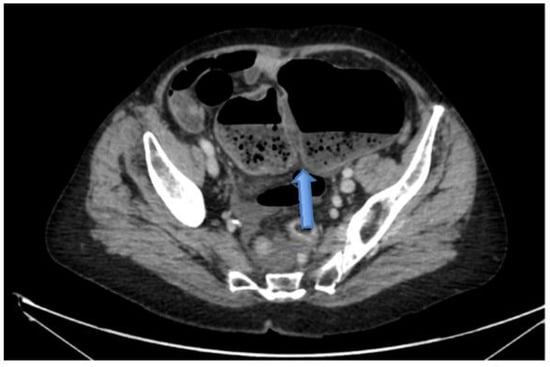

4.4.2. Computerised Tomography (CT) Scan

| CT Abdomen and pelvis | 15 | One patient operated without CT. |

| CV not described | 1 | |

| CV correctly identified | 14 (93.3%) | |

| Caecal diameter >10 cm | 10 (67%) | |

| Whirl sign | 12 (80%) | |

| Split-wall sign | 13 (86.6%) | |

| X-marks-the-spot sign | 14 (93.3%) | |

| Double transition point | 13 (86.6%) | |

| Ileocaecal twist | 13 (86.6%) | |

| Central appendix | 11 (73.3%) |